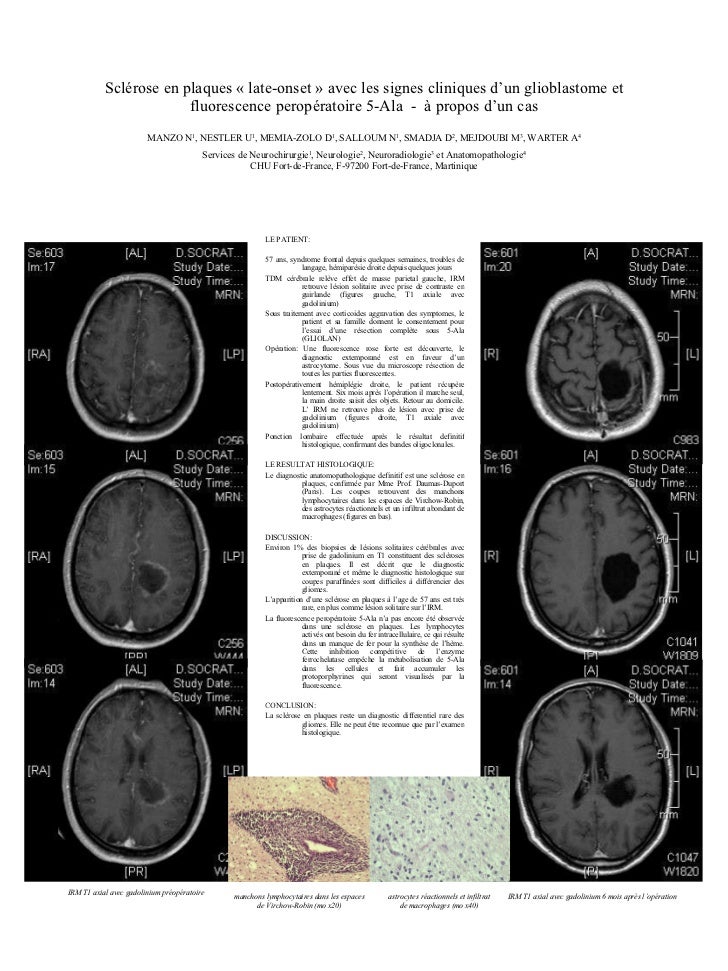

A Case Of Late Onset Multiple Sclerosis Mimicking Glioblastoma And Displaying Intraoperative 5 Aminolevulinic Acid Fluorescence Springerlink